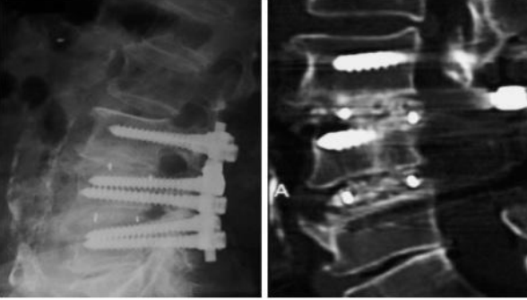

2.椎间远期融合效果好,沉降率低

● 椎间盘退变

◇常规的陈旧性椎间盘切除手术或需广泛减压的脊柱外科手术如:椎板切除、关节突切除、椎孔扩大成型等

◇对失败的椎间盘手术、再发性椎间盘突出、术后脊柱不稳等情况施行纠正手术

● 腰椎假关节

● 复位不理想的退变性脊柱滑脱或峡部滑脱